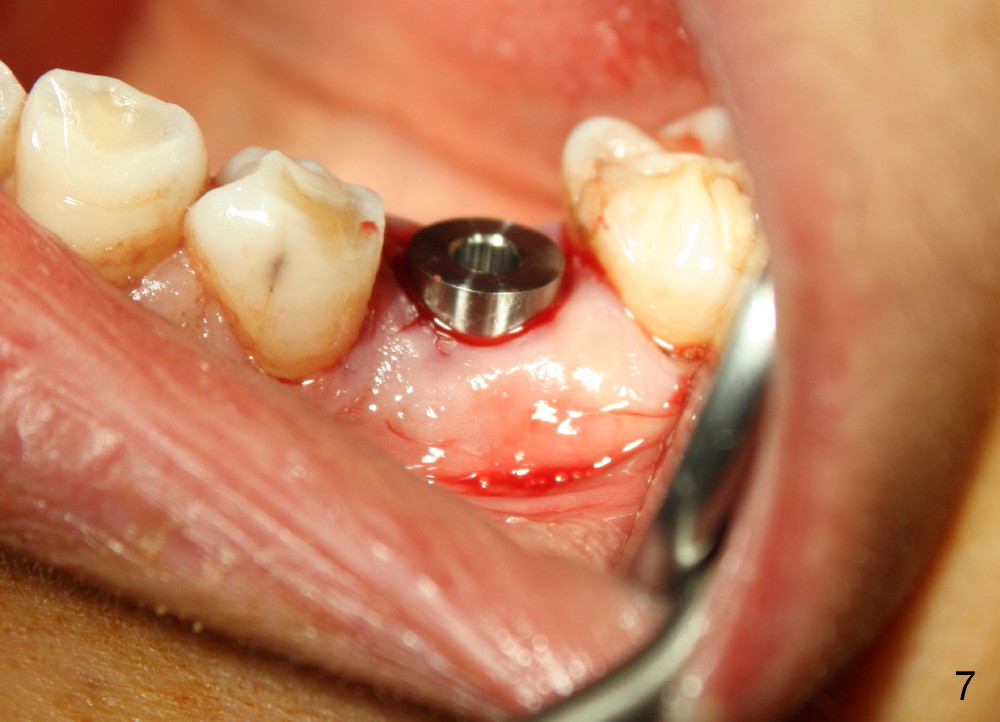

Taking multiple intraop X-ray is also necessary for depth adjustment (Fig.3-5). For example, when a 5x20 mm tap is inserted at the depth of 17 mm, it is close to the mental loop (Fig.4), whereas the binding to the bone is minimal. So a larger implant is to be placed at a shallower depth (Fig.5: 6x17 mm with insertion torque >60 Ncm). The shallower implant placement creates limited space for future abutment and crown (Fig.6,7). A short abutment will be used and the implant margin will be prepared as low as possible. As expected, the wound heals in a week (Fig.8).

Six months postop, bone density around the implant increases (Fig.9). There is slight gingival recession buccal to the implant (Fig.10 arrow). A short abutment is placed and prepared short (Fig.11 A); the margin is prepared as low as possible in the implant (I).